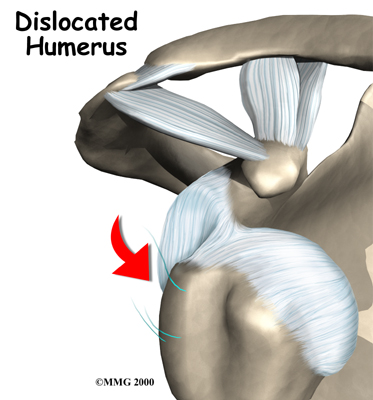

Shoulder instability means that the shoulder joint is too loose and is able to slide around too much in the socket. In some cases, the unstable shoulder actually slips out of the socket. If the shoulder slips completely out of the socket, it has become dislocated. If not treated, instability can lead to arthritis of the shoulder joint.

happen when a force overcomes the strength of the rotator cuff muscles and the ligaments of the shoulder. Nearly all dislocations are anterior dislocations, meaning that the humerus slips out of the front of the glenoid. Only three percent of dislocations are posterior dislocations, or out the back.

Sometimes the shoulder does not come completely out of the socket. It slips only partially out and then returns to its normal position. This is called subluxation.

Shoulder instability often follows an injury that caused the shoulder to dislocate. This initial injury is usually fairly significant, and the shoulder must be reduced. To reduce a shoulder means it must be manually put back into the socket. The shoulder may seem to return to normal, but the joint often remains unstable. The ligaments that hold the shoulder in the socket, along with the labrum (the cartilage rim around the glenoid), may have become stretched or torn. This makes them too loose to keep the shoulder in the socket when it moves in certain positions. An unstable shoulder can result in repeated episodes of dislocation, even during normal activities. Instability can also follow less severe shoulder injuries.

The shoulder may become so loose that it starts to dislocate frequently. This can be a real problem, especially if you can't get it back in the socket and must go to the emergency room every time. A shoulder dislocation is usually very obvious. The injury is very painful, and the shoulder looks abnormal. Any attempted shoulder movements cause extreme pain. A dislocated shoulder can damage the nerves around the shoulder joint.

When you go to the doctor with a dislocated shoulder, X-rays are necessary to rule out a fracture.

X-rays are usually done after the shoulder is put back into joint. This allows your doctor to make sure the joint is back in place.